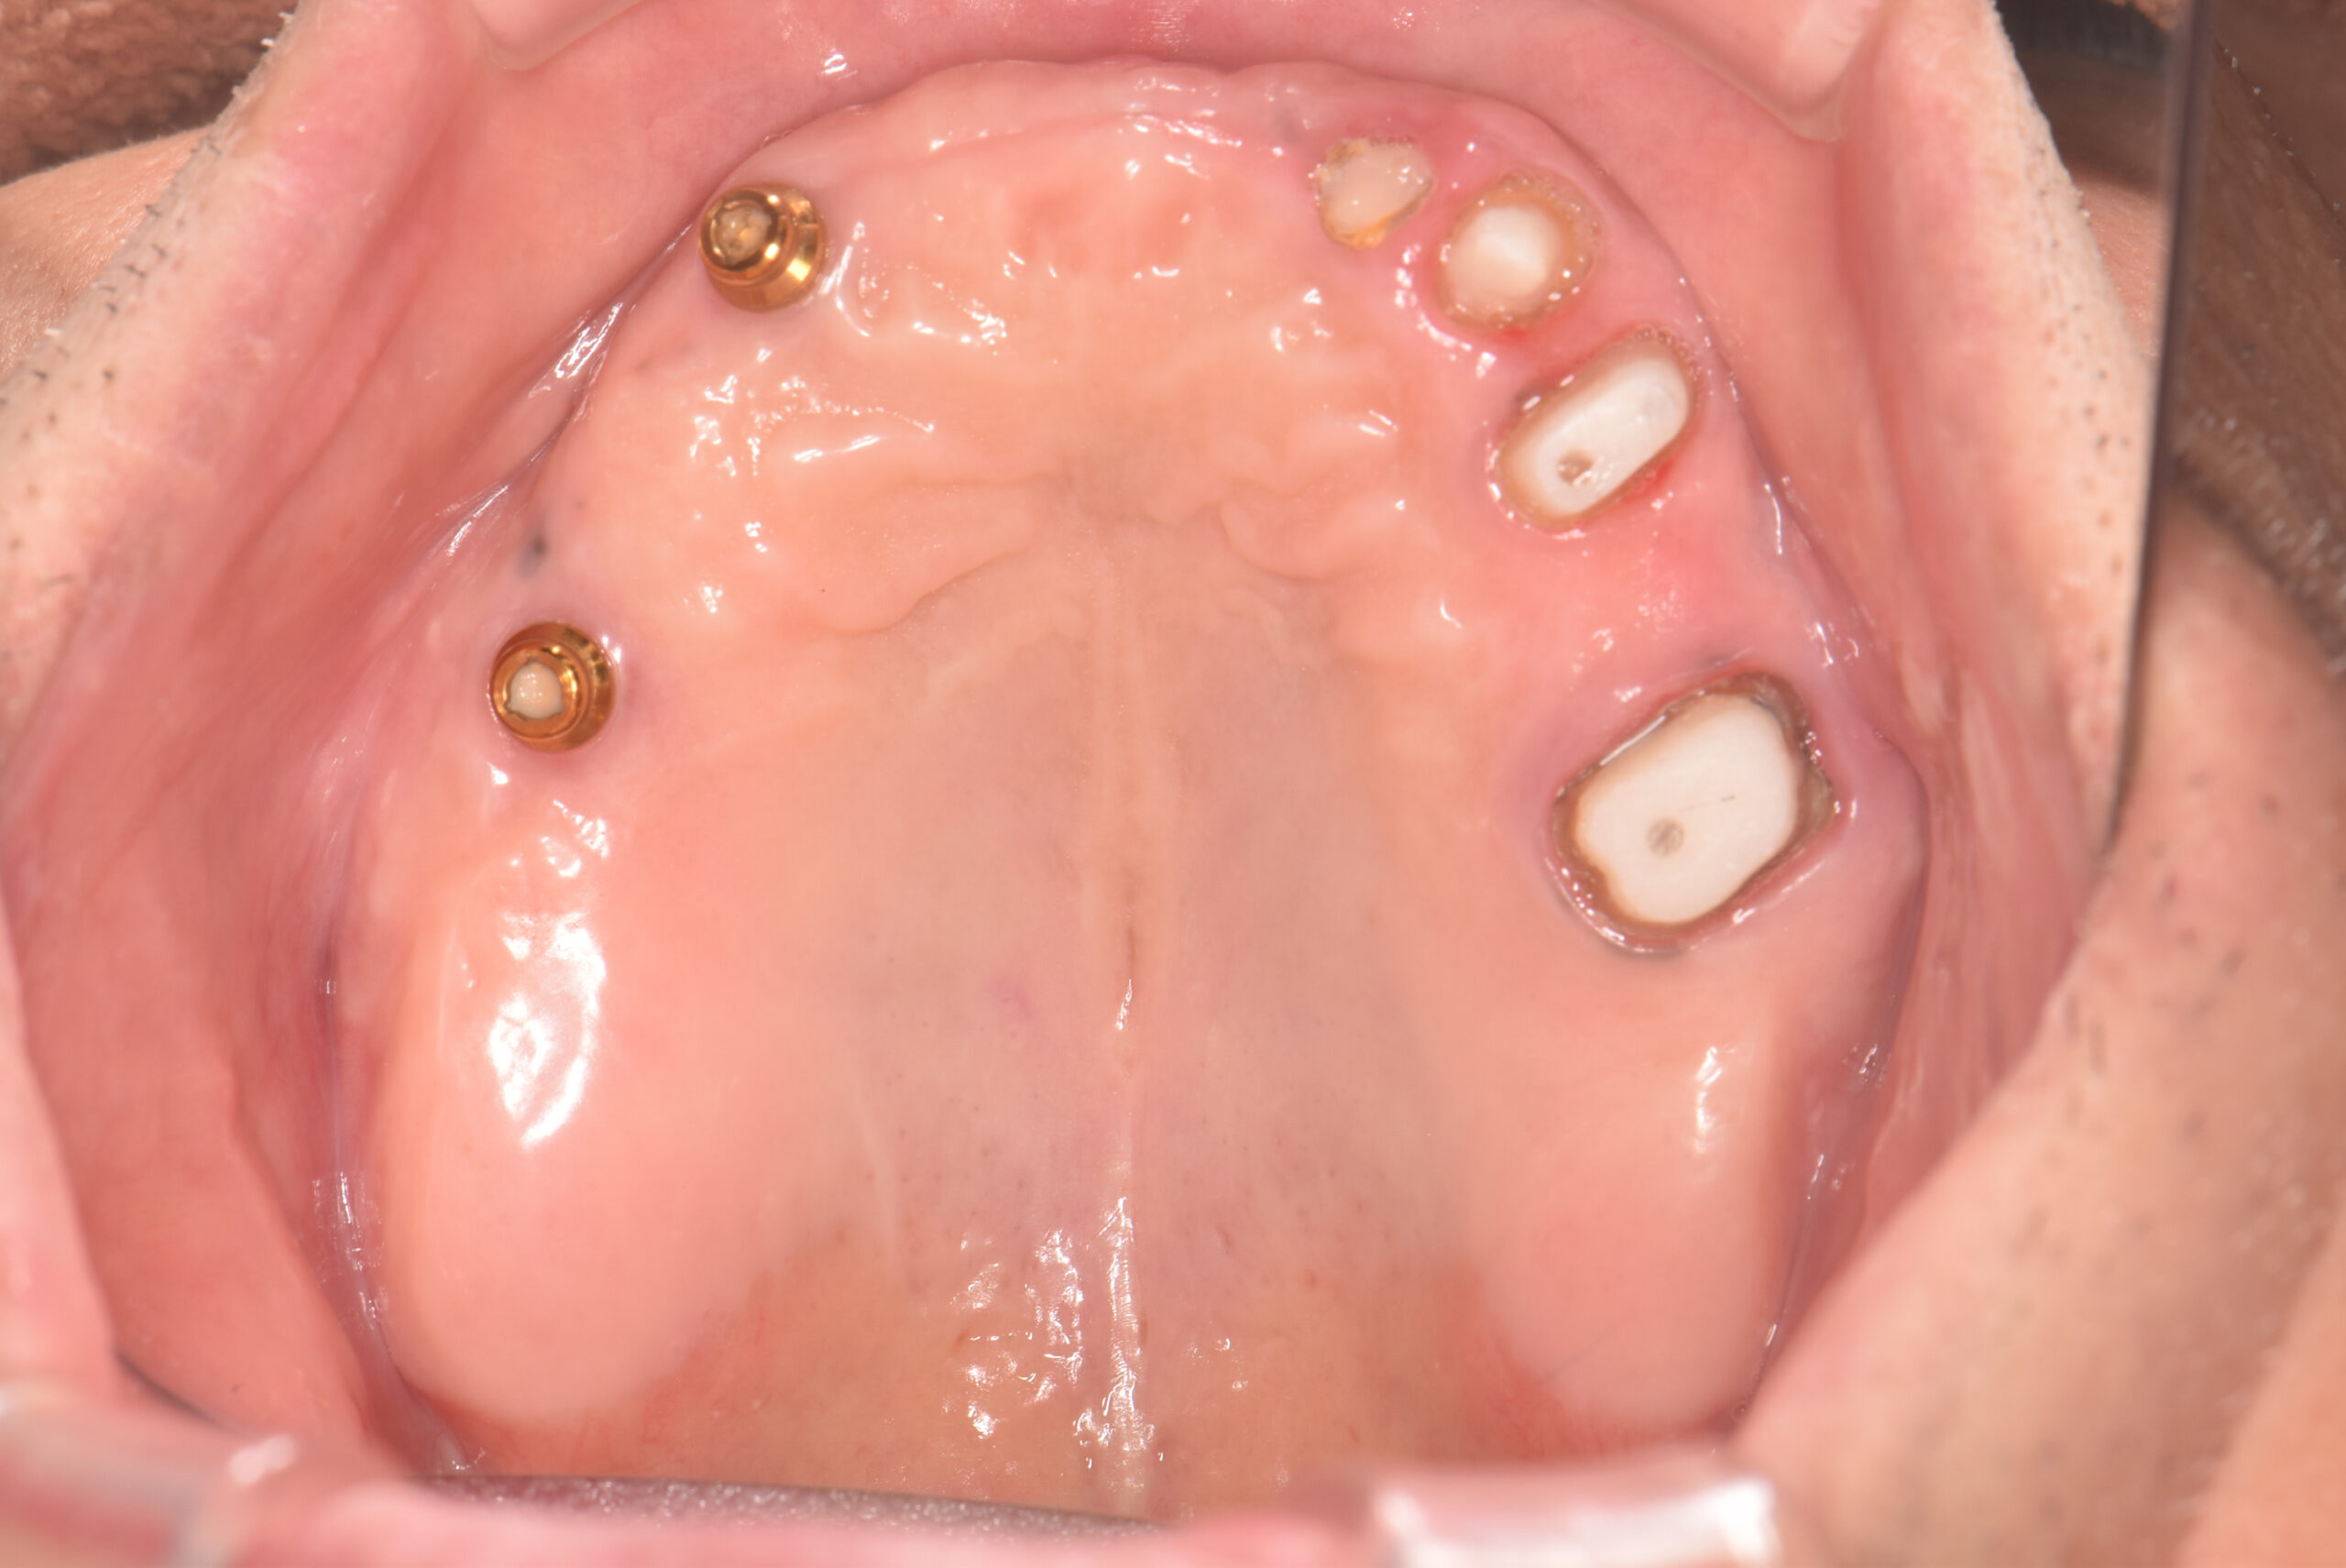

右上6・3番目にインプラント体を埋入し、その上に専用の義歯(オーバーデンチャー)をセット。左上3456にメタルボンドブリッジをセットした患者様の口腔内です。

上顎にインプラント埋入後の口腔内です。